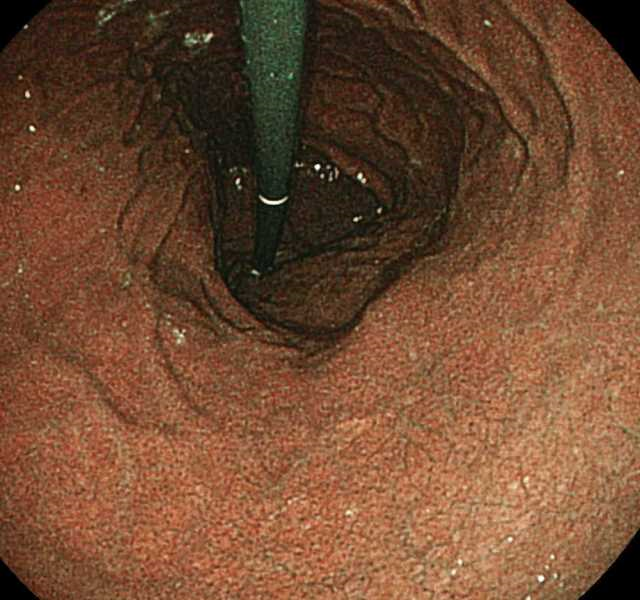

通常の見え方です(白色光)。

内視鏡の光の波長の設定を変えると血管の見え方が強調されます。

これによって病変の視認性が高まります。